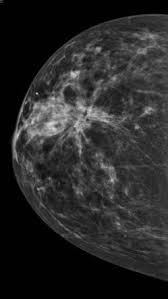

Принято различать простые (гомогенные) и сложные (гетерогенные) кисты молочных желез. Простые кисты небольших размеров могут наблюдаться в динамике и не имеют злокачественного потенциала. Хирургическое лечение показано в случаях неэффективности консервативной терапии.

простая киста молочной железы.